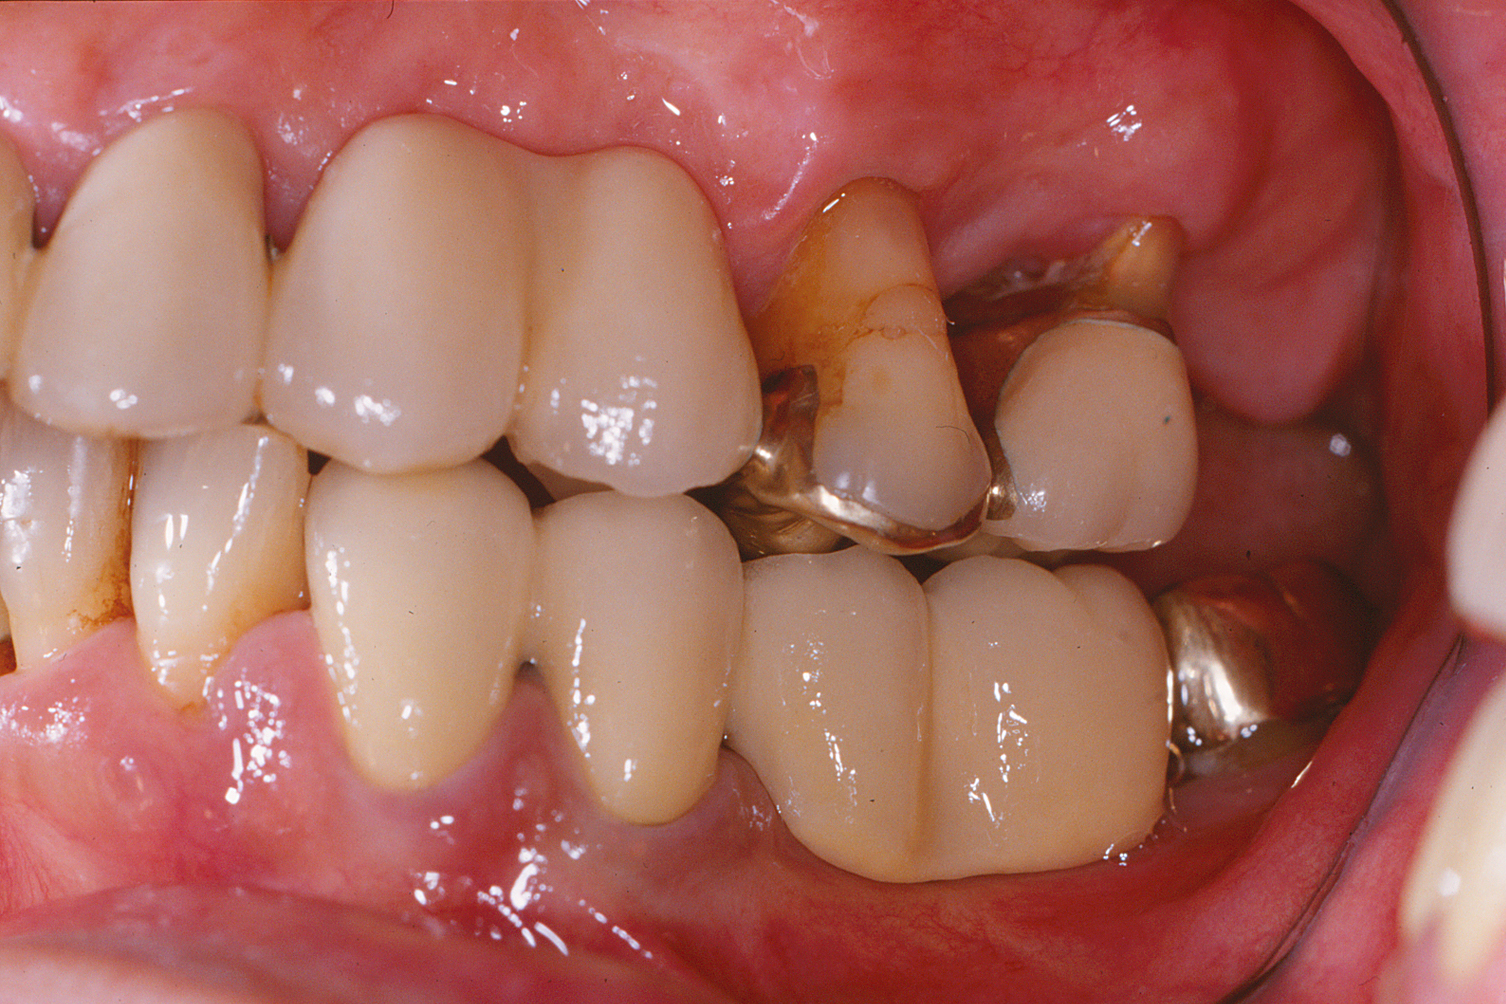

本症例は50才代後半の男性で、全顎的な歯周治療を希望して来院。

精査した結果、全顎的に中等度から重度の歯周炎が認められ、特に左上犬歯と第一小臼歯、第2大臼歯は保存不可能であった。また、左上大臼歯も保存には適さないと判断したが、抜去してしまうと義歯の装着を余儀なくされるため、近心頬側根のみ抜去を行った。臼歯部は外科を行っている。術後写真は、術後3年の状態であるが歯周組織の状態は安定している。